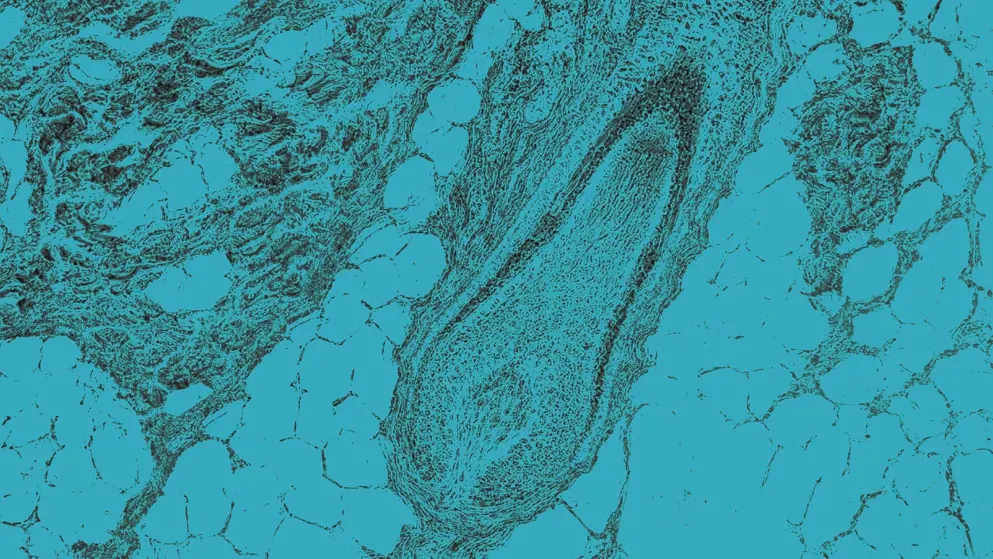

Alopecia areata (AA) is caused by the immune system erroneously attacking hair follicles, leading to inflammation. While researchers are not entirely sure why this immune attack occurs, they suspect that both genetic and environmental factors contribute. AA mainly causes hair loss, though it can sometimes cause changes in the nails, such as pits. People with this condition are generally healthy and exhibit no other symptoms.